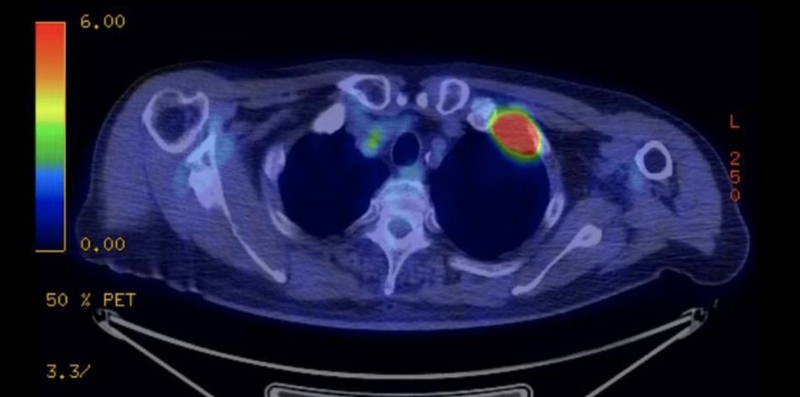

Chụp cắt lớp điện toán phát xạ Positron (PET) là một công nghệ hình ảnh khám lâm sàng, cung cấp hình ảnh ba chiều và chức năng của toàn bộ cơ thể tương đối tiên tiến trong lĩnh vực y học hạt nhân. Đây là công nghệ duy nhất sử dụng hình thái giải phẫu để thực hiện hình ảnh chức năng, chuyển hóa và thụ thể, không xâm lấn và hiện là một trong những phương pháp lâm sàng tốt nhất để chẩn đoán và hướng dẫn điều trị khối u.

Chụp PET được thực hiện bằng cách tiêm vào cơ thể chất đánh dấu PET như glucose, protein, axit nucleic và axit béo đánh dấu hạt nhân phóng xạ có thời gian tồn tại ngắn, sau khi được tiêm vào cơ thể con người, thông qua sự tích tụ chất trong quá trình trao đổi chất, nó có thể phản ánh các hoạt động trao đổi chất của sự sống, từ đó đạt được mục đích chẩn đoán. Ở các tế bào ung thư, chúng có khả năng chuyển hóa cao, quá trình chuyển hóa chất tiêm vào diễn ra mạnh mẽ và tích tụ nhiều hơn, những đặc điểm này có thể được phản ánh qua hình ảnh, nhờ đó có thể chẩn đoán và phân tích các tổn thương.